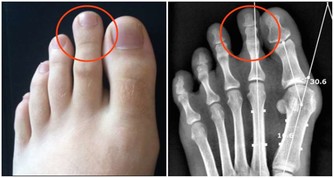

當用指甲輕掐小腳趾外側的至陰穴痛如針刺時,膀胱經就算是打通了。

至陰:小腳趾外側指甲旁。艾灸可轉胎。